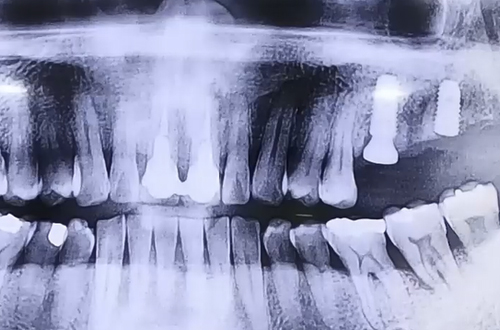

AFTER

따라서 오른쪽은 잇몸 치료로 더 나빠지지 않도록 관리를 해 드리고

왼쪽으로 음식을 드실 수 있도록 왼쪽은 발치 후 임플란트를 계획했습니다.

왼쪽 위 어금니 두 개를 발치하게 되었는데,

하나는 잇몸 뼈의 상태가 괜찮아 즉시 식립으로 진행하였고

하나는 잇몸 뼈가 단단하지 않아서 염증을 깨끗이 치료하고 뼈이식을 한 뒤

기다렸다가 진행하는 지연 식립 임플란트로 진행한 사례입니다.